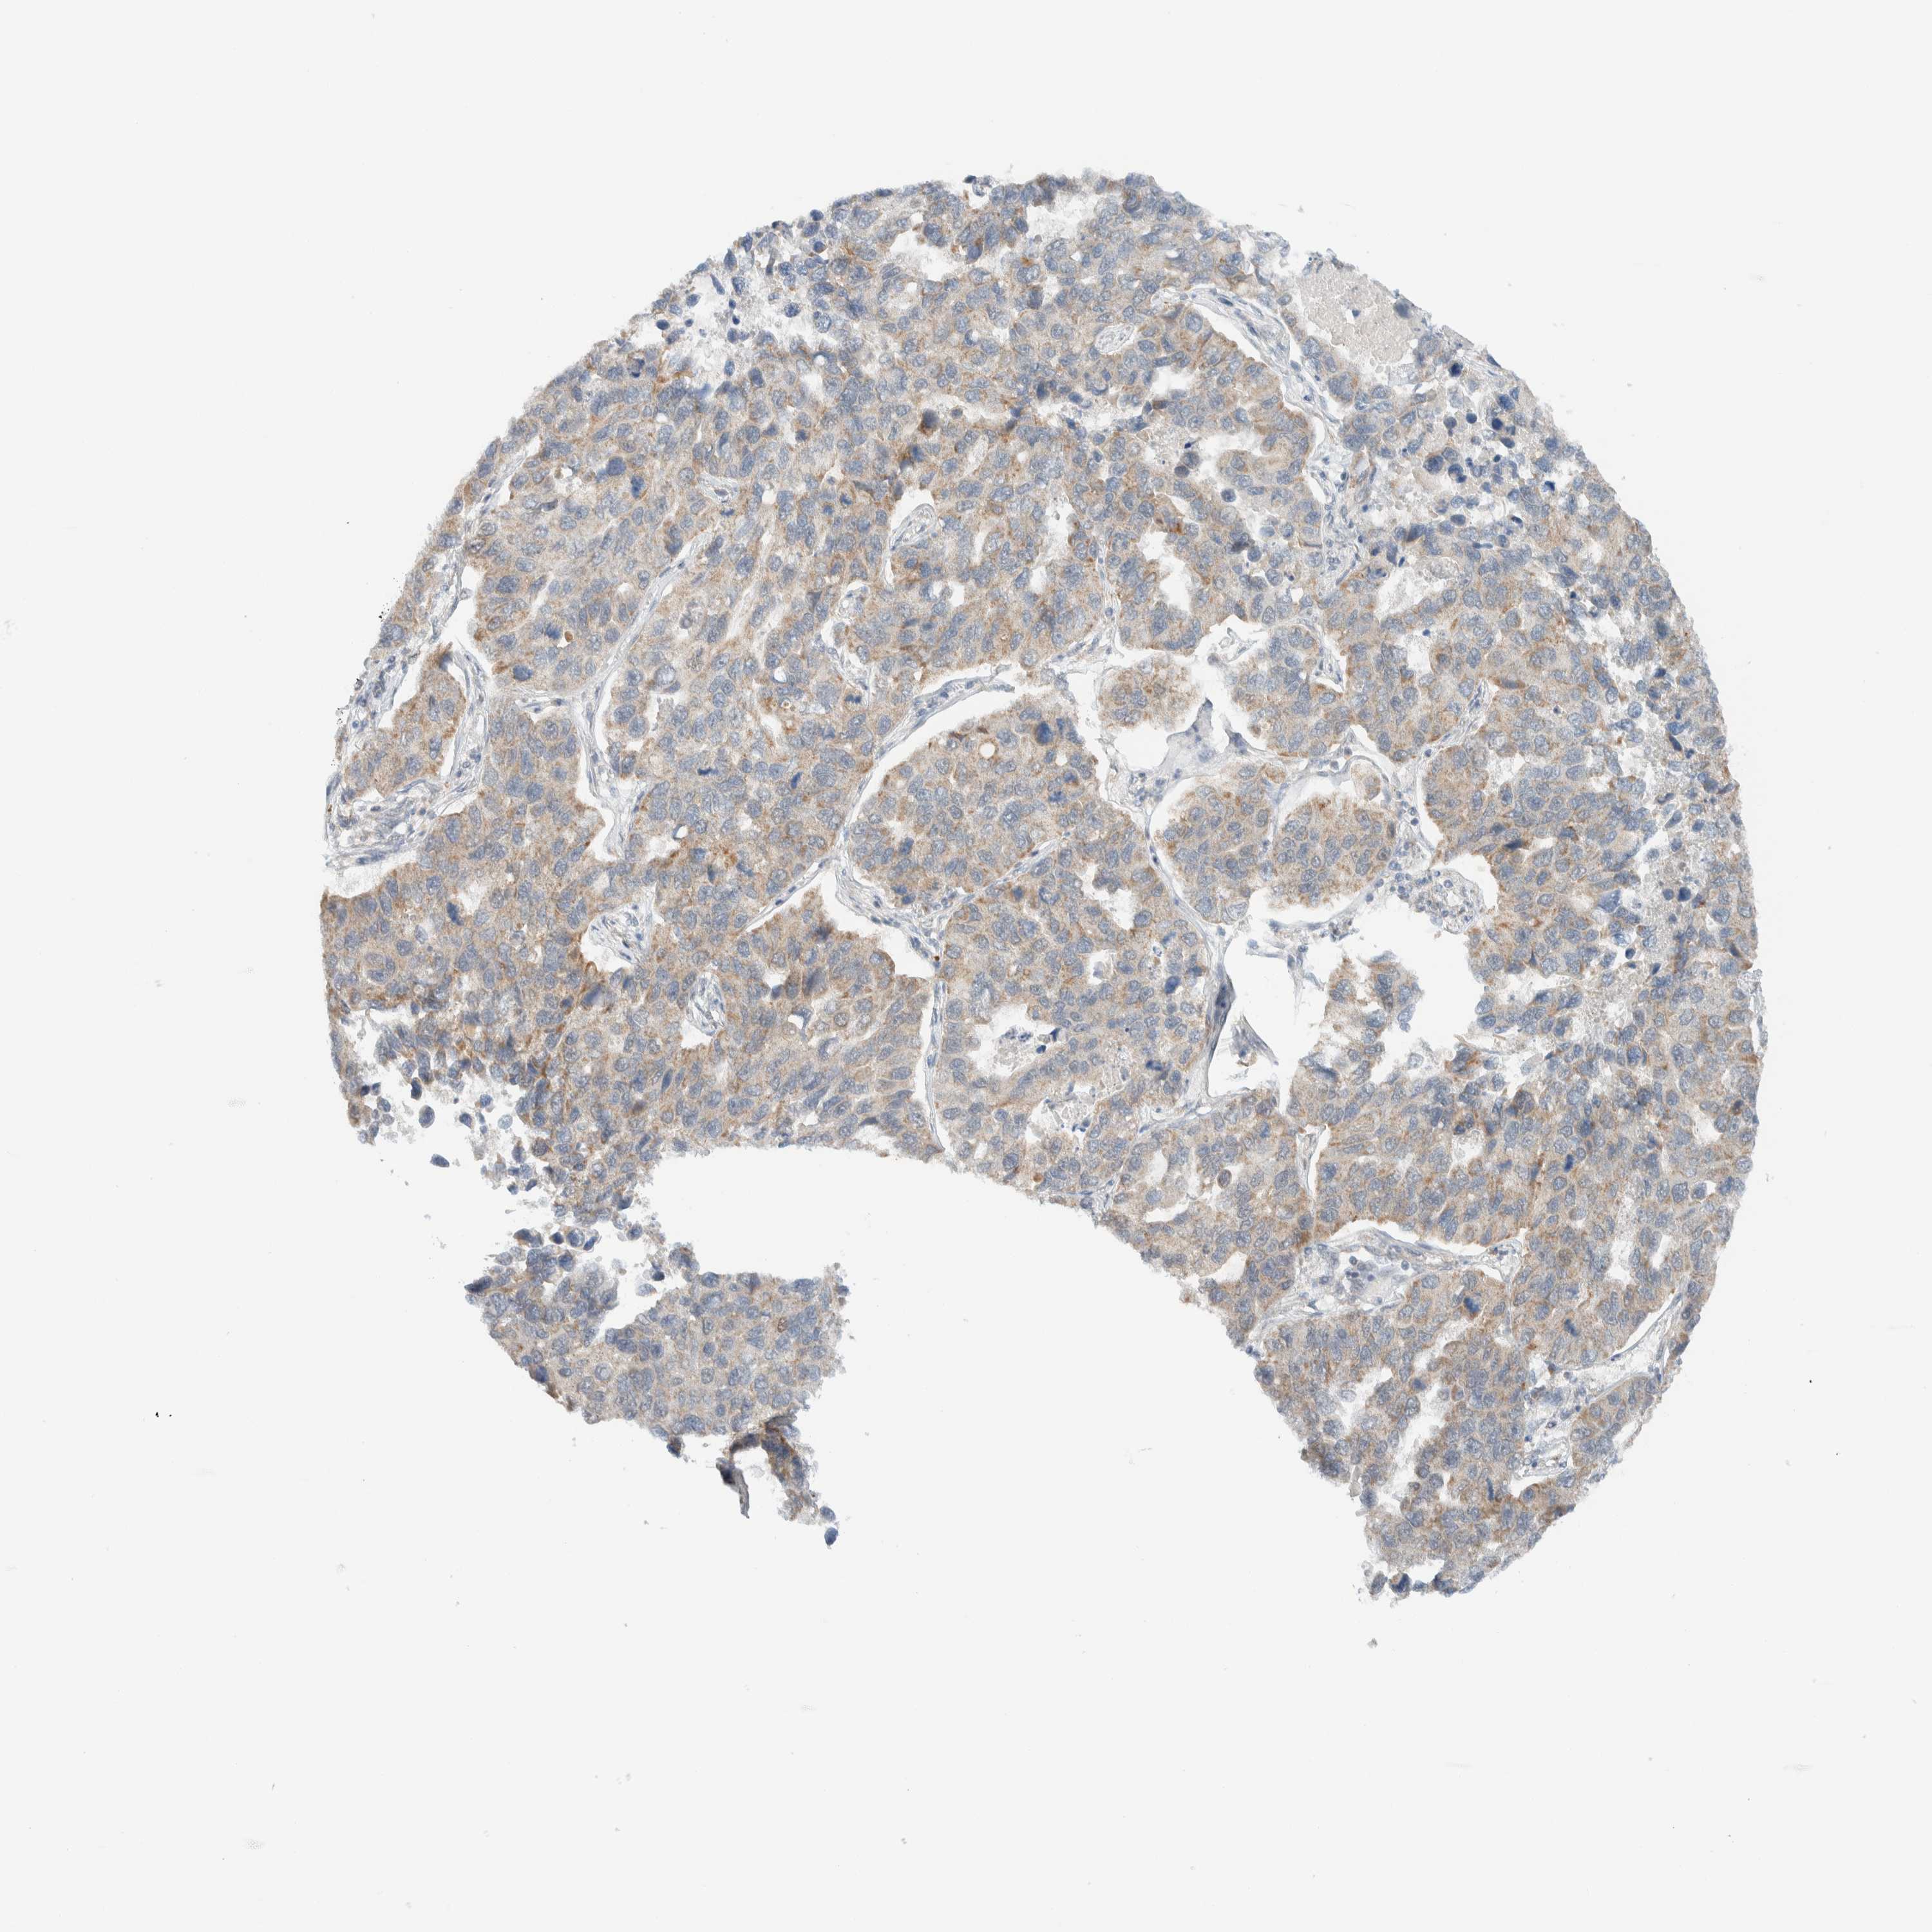

LUNG ADENOCARCINOMA (TCGA) - Interactive survival scatter ploti

The Survival Scatter plot shows the clinical status (i.e. dead or alive) for all individuals in the patient cohort, based on the same data that underlies the corresponding Kaplan-Meier plots. Patients that are alive at last time for follow-up are shown in blue and patients who have died during the study are shown in red.

The x-axis shows the expression levels (FPKM) of the investigated gene in the tumor tissue at the time of diagnosis. The y-axis shows the follow-up time after diagnosis (years). Both axes are complimented with kernel density curves demonstrating the data density over the axes. The top density plot shows the expression levels (FPKM) distribution among dead (red) and alive patients (blue). The right density plot shows the data density of the survived years of dead patients with high and low expression levels respectively, stratified using the cutoff indicated by the vertical dashed line through the Survival Scatter plot. This cutoff is automatically defined based on the FPKM cutoff that minimizes the p-score. The cutoff can be changed by dragging the vertical line or by entering a cutoff value in the square labeled "Current cut-off".

Under the Survival Scatter plot the p-score landscape (black curve; left axis) is shown together with dead median separation (red curve; right axis). Dead median separation is the difference in median mRNA expression between patients who have died with high and low expression, respectively. It is calculated as follows: median FPKM expression of dead patients with high expression - median FPKM expression of dead patients with low expression. This is intended to aid the user in visually exploring custom cutoffs and the associated p-scores and dead median separation.

Individual patient data is displayed and can be filtered by clicking on one or more of the category buttons on the top of the page. Categories describing expression level and patient information include: high, low, alive, dead, female, male and tumor stages. The scale of the x-axis can be toggled between linear and log-scale by clicking on the "x log" button. Mouse-over function shows TCGA ID, patient information and mRNA expression (FPKM) for each patient.

& Survival analysisi

Kaplan-Meier plots summarize results from analysis of correlation between mRNA expression level and patient survival. Patients were divided based on level of expression into one of the two groups "low" (under cut off) or "high" (over cut off). X-axis shows time for survival (years) and y-axis shows the probability of survival, where 1.0 corresponds to 100 percent.

MRPL41 is not prognostic in Lung Adenocarcinoma (TCGA)